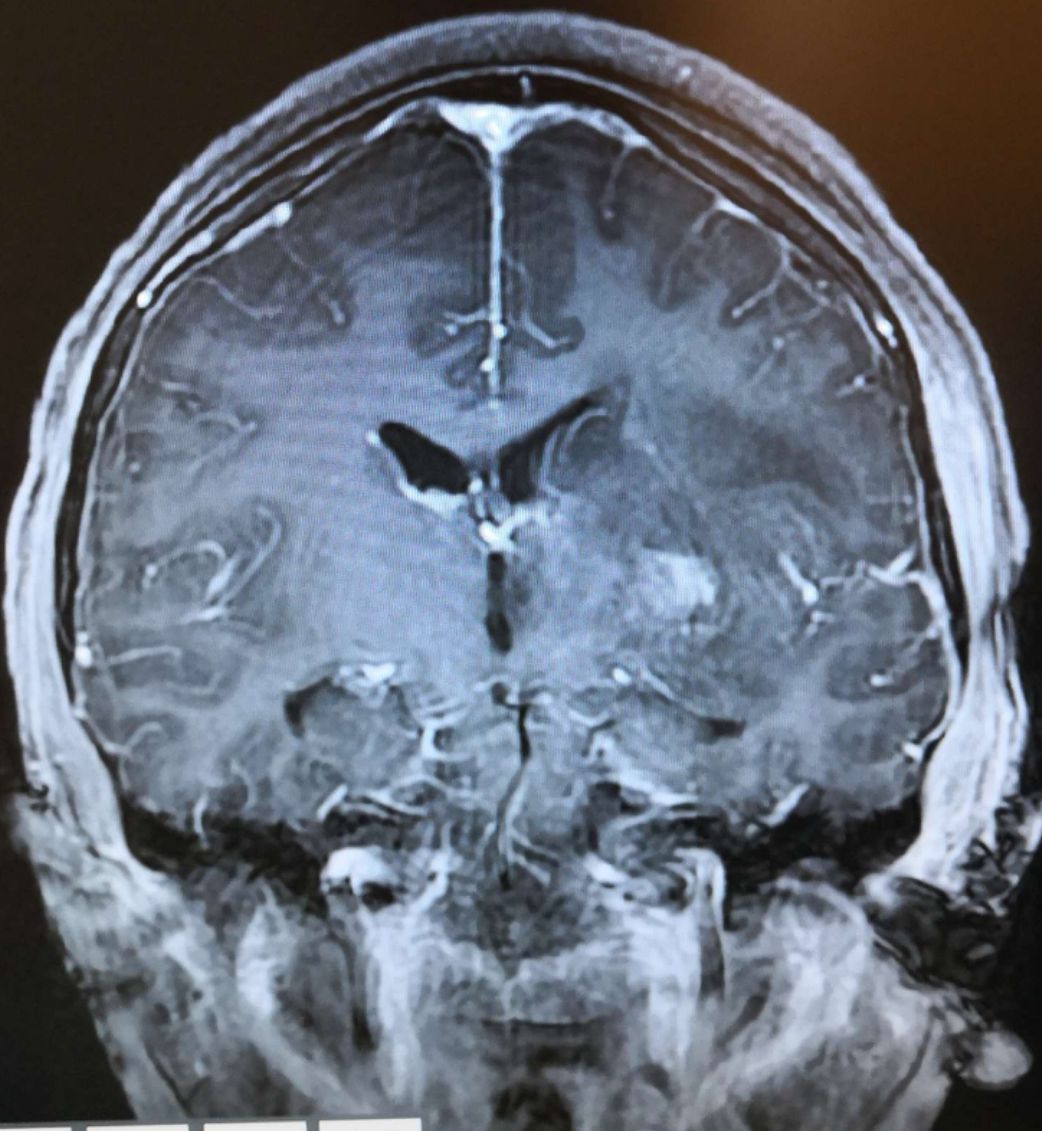

术前头颅MRI增强扫描显示:病灶强化明显,脑室受压,中线移位明显。

术前头颅MRI 增强扫描显示:病灶强化明显,脑室受压。

术前头颅MRI 增强扫描显示:病灶强化明显,脑室受压,中线移位明显。